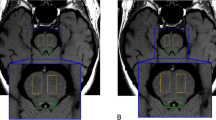

During both MRI scan sessions, the participants underwent a whole-brain 3D T1-weighted (Grabner et al. 2006) and a brainstem-zoomed T1-weighted turbo spin echo (TSE) structural scan (Sasaki et al. 2006) in a 3 T-TX Philips scanner equipped with a 32-channel head coil. The whole-brain volume (field of view (FOV): 224 × 177.33 × 168 mm; 140 slices; 0.87 × 0.87 × 1.2 mm; TR: 9.7 ms; TE: 4.5 ms; flip angle 8o; acquisition matrix: 192 × 152; scan duration: 4.9 min) was used to facilitate co-registration between scan sessions and subsequent normalization to the standard 0.5-mm MNI template. The TSE scan sequence was used to detect the LC and had similar sequence parameters as the ones reported in prior literature (FOV: 180 × 180 × 22.95 mm; 14 slices; reconstruction resolution 0.35 × 0.35 × 1.5 mm, gap of 10%; TSE factor: 3; TR: 500 ms; TE: 10 ms; flip angle 90o; acquisition matrix: 256 × 204; scan duration: 7 min) (see Fig. 1 for an example).